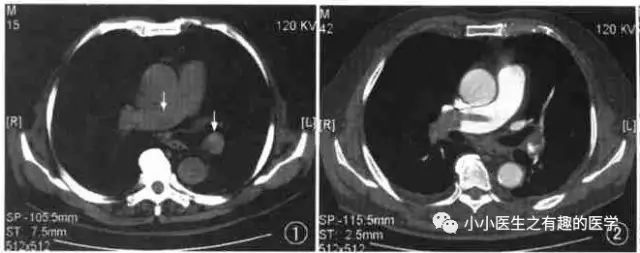

如图,高密度影的那一条。

不怕,有增强CT证实。

是不是很有趣。

再来一个图。

仔细看,有端倪。

增强CT可以核实。

很明显,患者做了CT平扫,我们要仔细阅片,发现可疑,及时增强CT,要不然就漏诊了。